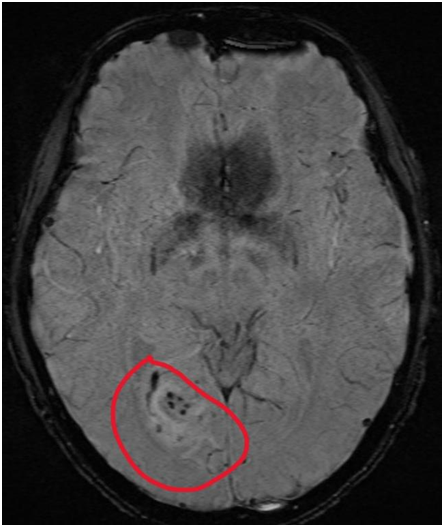

不幸的是,他最终被确诊为“感染性心内膜炎合并颅内多发性脑梗死、肾梗死导致等多器官栓塞危象”,住进了港大深圳医院心脏大血管外科病房。

多发性脑梗死已导致小官一侧眼睛偏盲,传统的开胸换瓣手术虽然可以解决心脏问题,但需要进行终生的抗凝治疗。

脑部多发梗塞出血灶